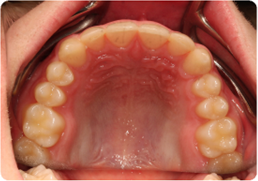

Each case shows the front view and an arch or side view, before and after BioLign Method-guided treatment.

All cases treated within 6–12 months.

Crowding with irregular gaps resolved into even alignment